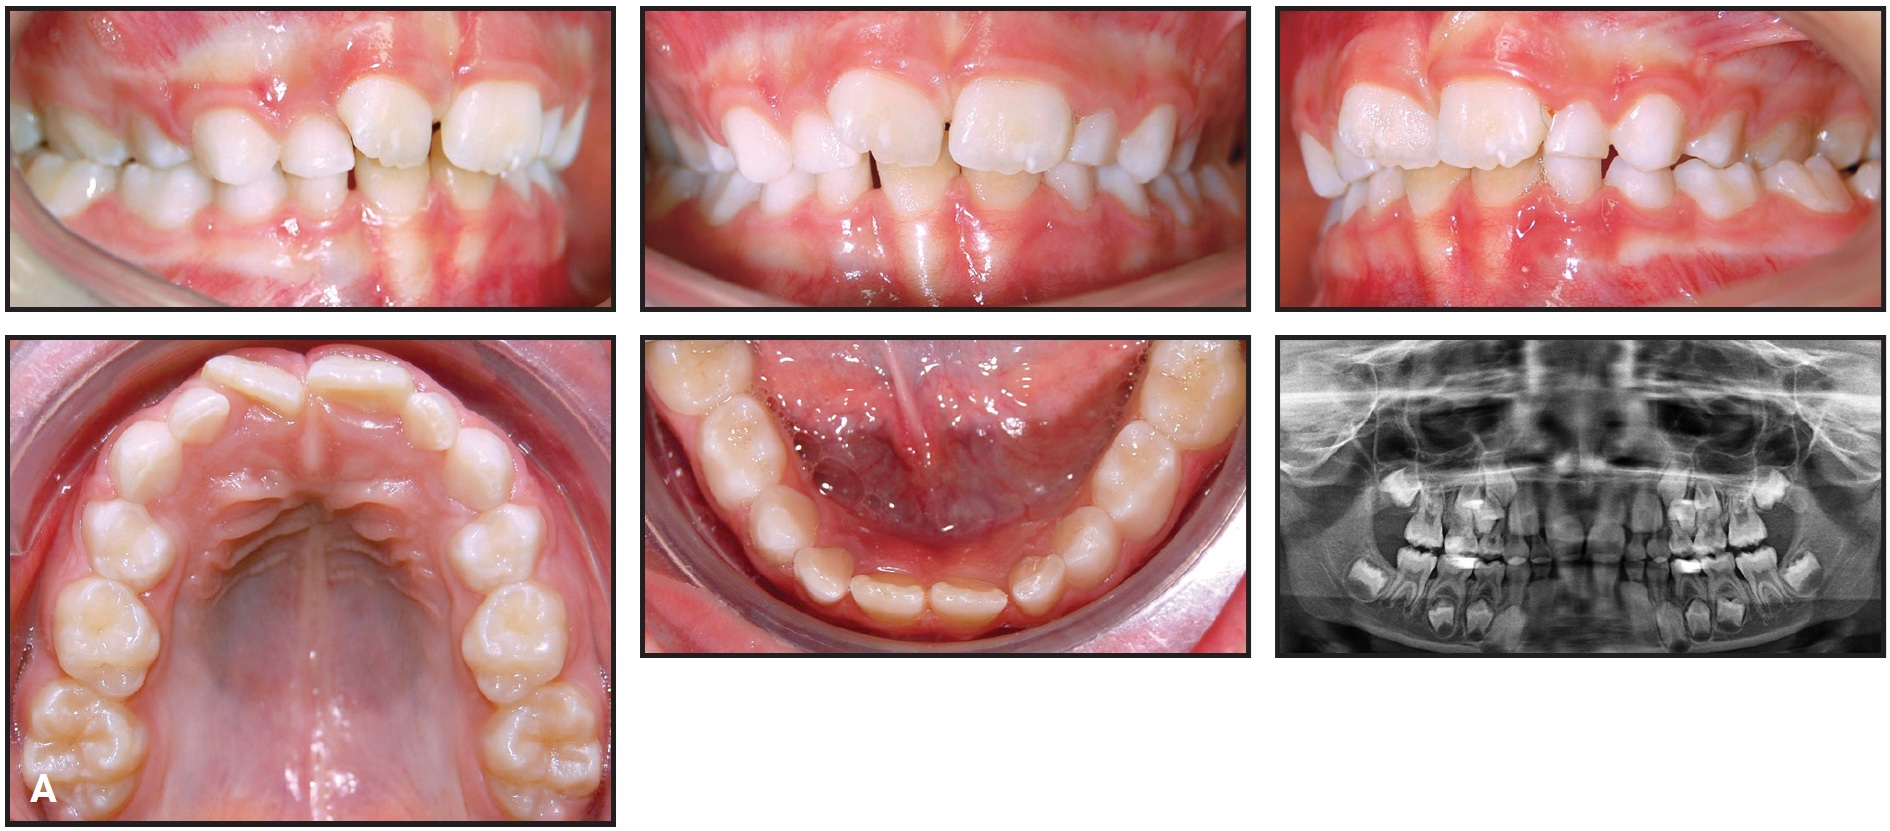

Fig. 7 Case 2. A. 6-year-old female patient with maxillary transverse deficiency and bilateral crossbite before treatment (continued in next image).

Fig. 7 (cont.) Case 2 B. Arch-width measurements on STL digital cast obtained from laboratory scan of polyvinyl siloxane impressions.

A Self Expander was bonded rather than banded to the upper first deciduous molars, with extensions to the canines (Fig. 8).

The patient was checked six times during seven months of active expansion, and the Self Expander was then left in place for three months of retention. The crossbite was corrected, the maxilla was expanded enough to allow eruption of the permanent lateral incisors, and the first permanent molars showed spontaneous expansion and derotation, guided by the occlusion (Fig. 9).